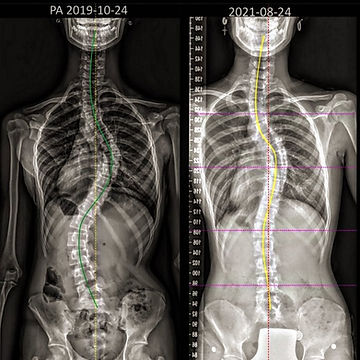

With the right application, you can realign your bones.

With daily effort, understanding and retensioning, your muscles will steer your bones into alignment.